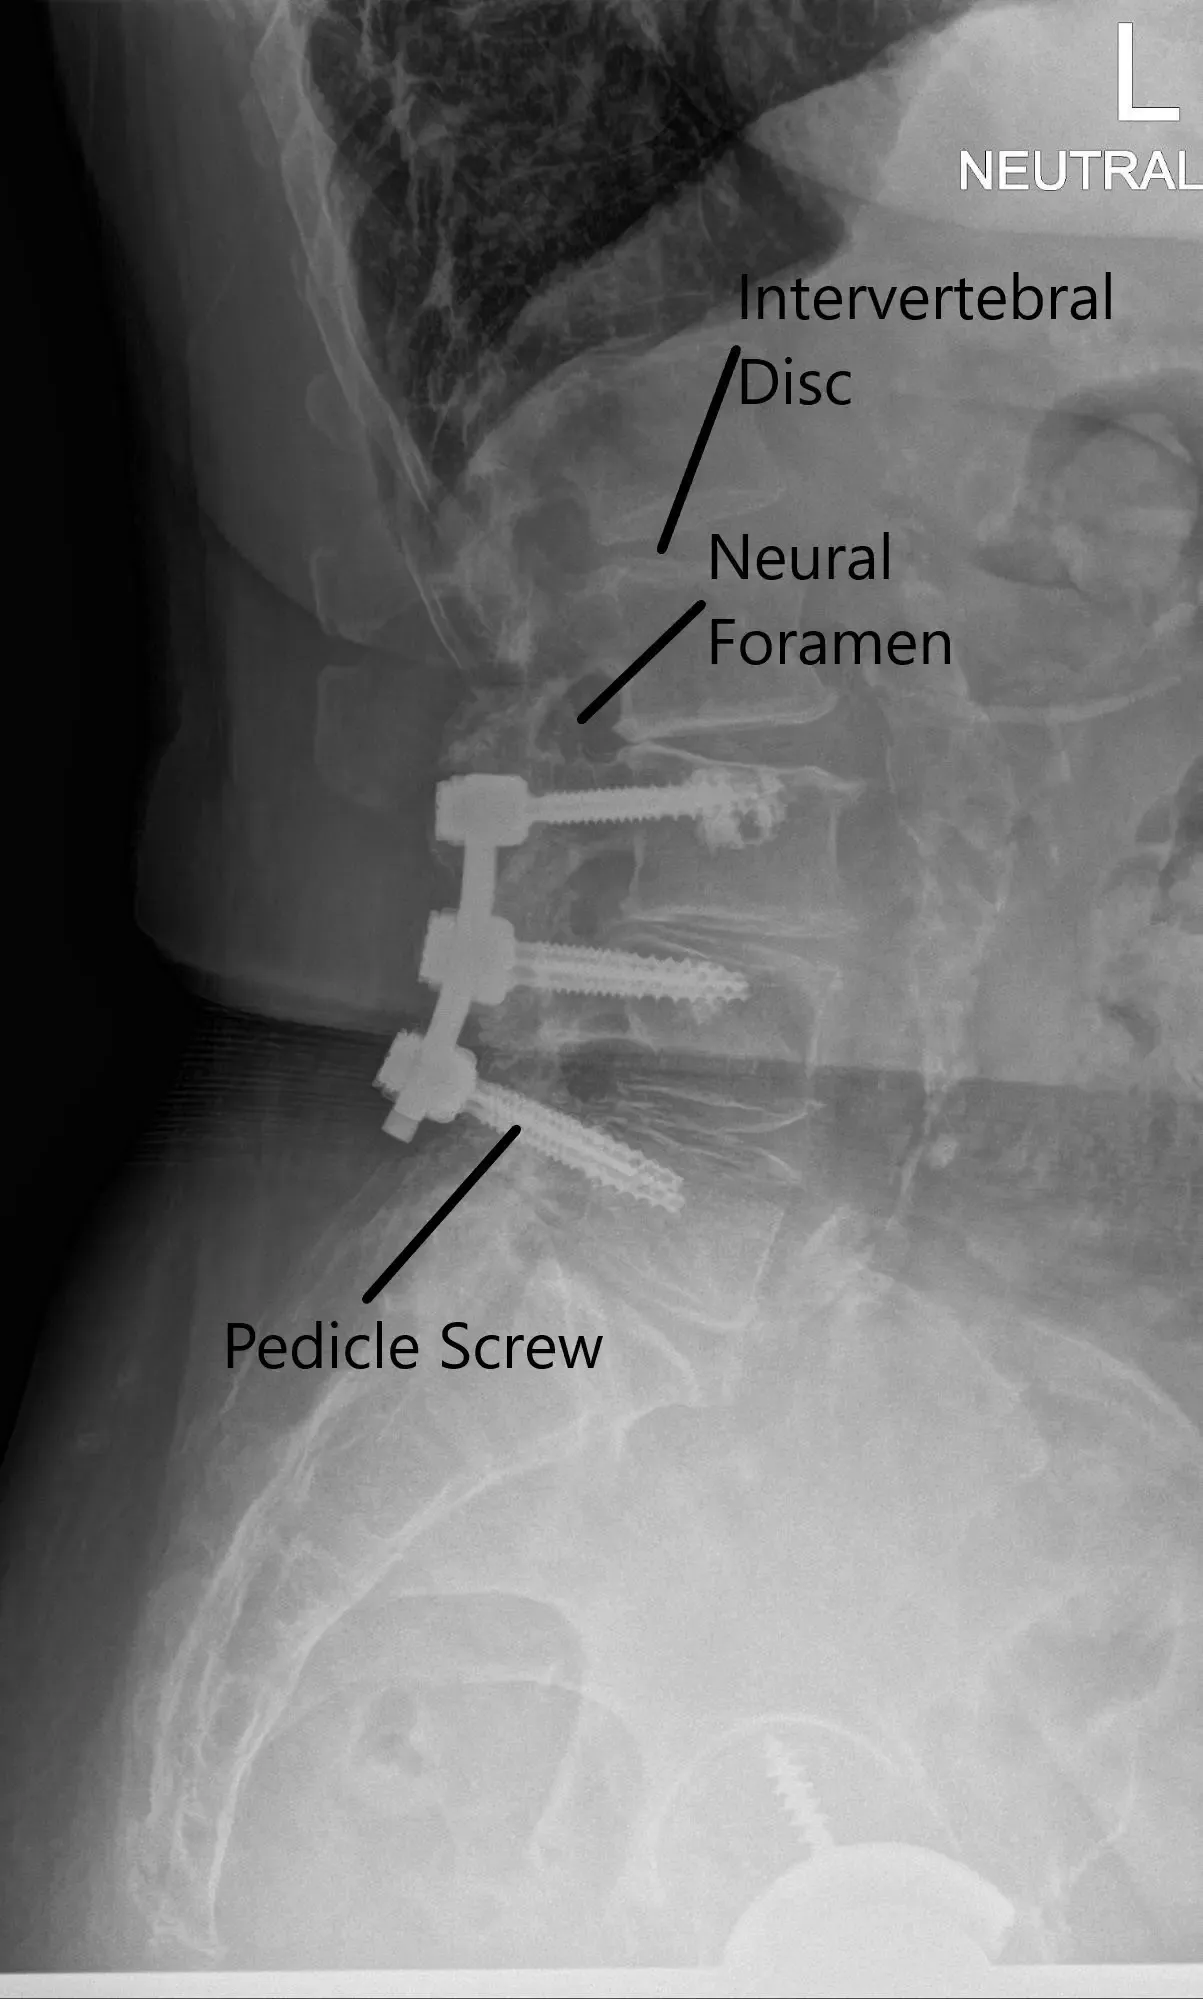

X-ray of the LS spine in AP and Lateral views.

CT scan signs of early screw loosening are seen. However, signs of bony ankylosis from L3-5 are also present. Degenerative spinal stenosis at L2-3 was present and was relatively unchanged since the most recent prior exam in 2018 but demonstrates progressive stenosis over the sequence of scans. MRI showed adjacent segment disease at L2-3 and L5-S1 with nerve root compressions.